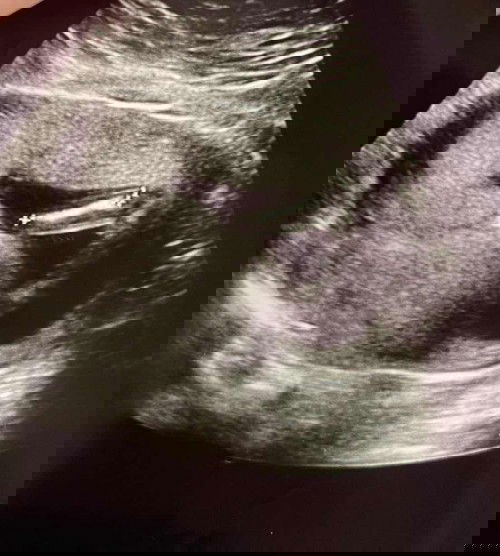

Gender baby 18weeks

Boy ke girl ni? Doktor taknak bgtahu dia kata awal lagi tapi nampak mcm boy. Apa pendapat mummy2 yg berpengalaman? Excited nk beli barang. First baby 🥰

Macam boy sis. Apape pun beli la baju putih dulu. Hehhe..#TAPSupermoms